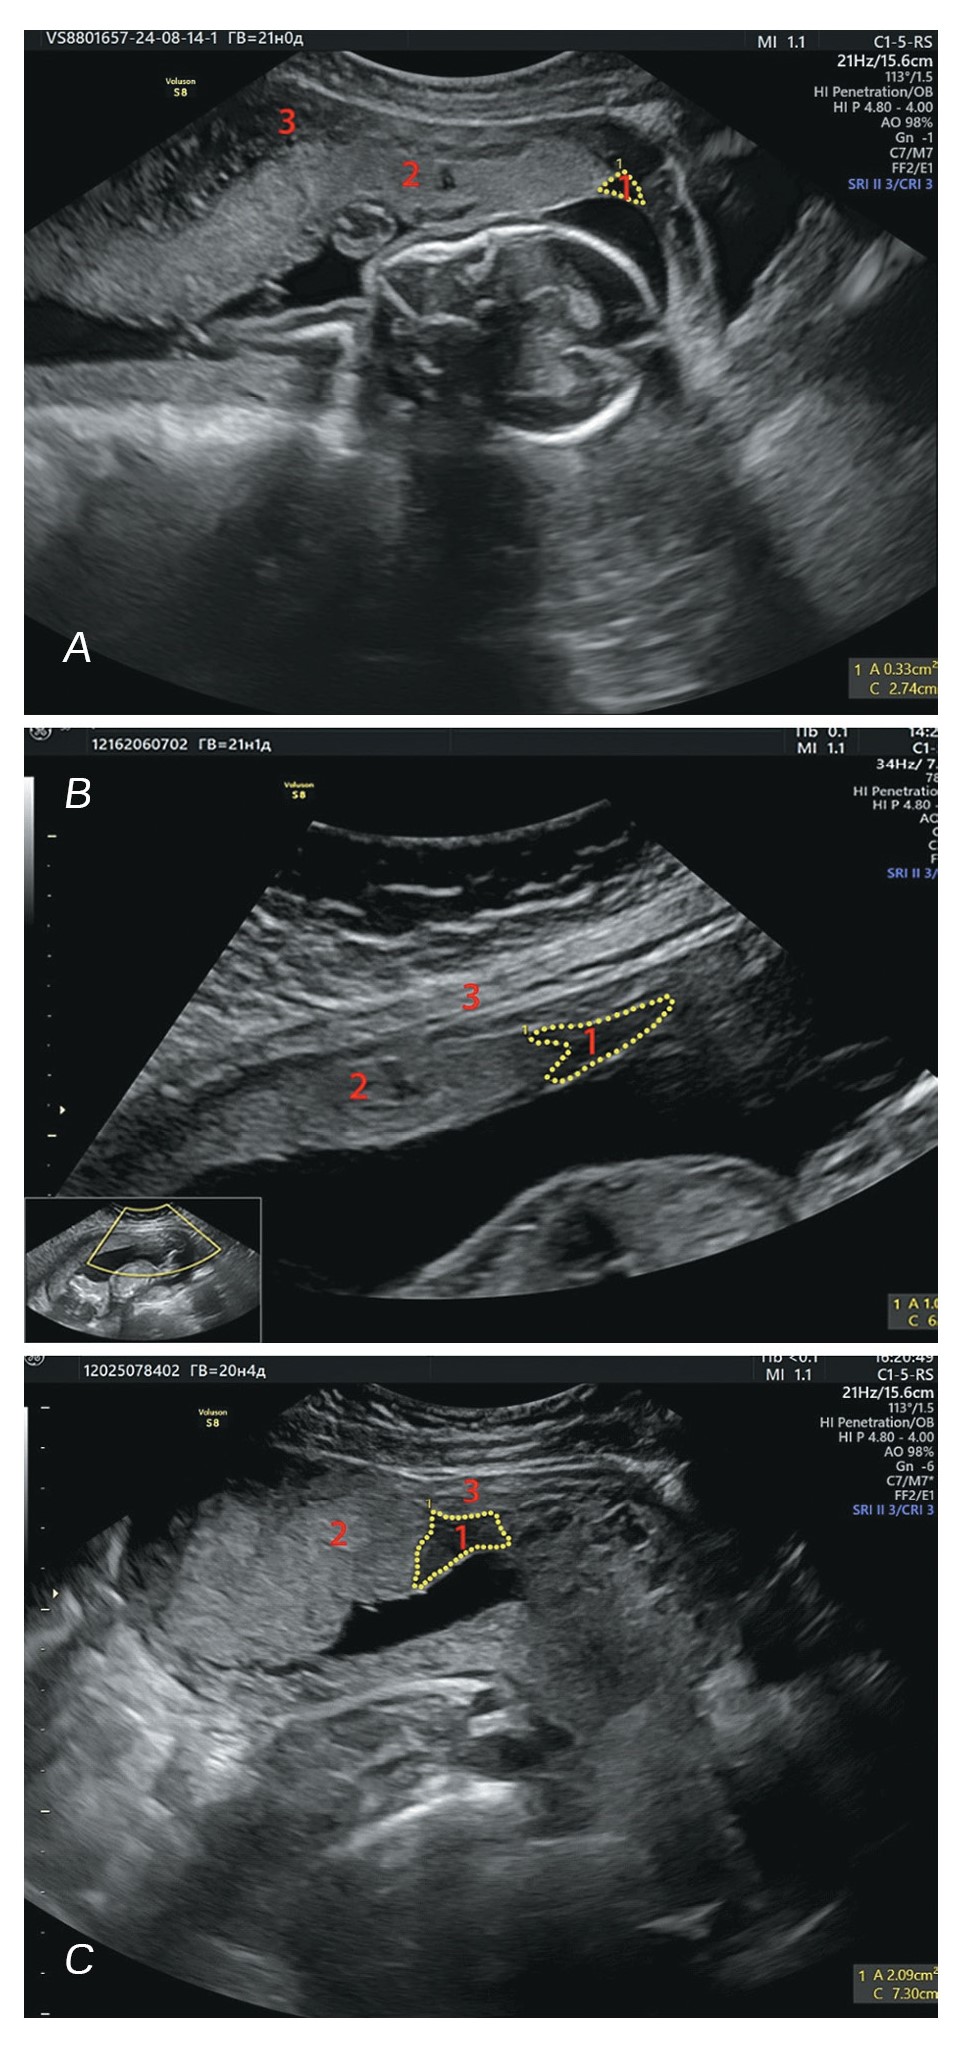

In the ultrasonic scans, the marginal sinus is shown as a space of varied shaped. The section form of the marginal sinus is closer to triangular (Fig. 4А) in 40% of the cases; the swept (Fig. 4B) and irregular (Fig. 4C) shapes being registered in 30% of the cases each, respectively (Fig. 4).

Figure 4. Various shapes of the edge sine slice. Ultrasound scan of the placenta in the B-mode. A – triangular, gestational age 20 weeks 6 days; B – swept, gestational age 21 weeks 1 day, C – incorrect, gestational age 20 weeks 4 days. 1 – marginal sinus; 2 – placenta; 3 – uterine wall.

Рисунок 4. Различные формы среза краевого синуса. Ультразвуковая сканограмма плаценты в В-режиме. А – треугольный, гестационный возраст 20 недель 6 дней; B – стреловидный, гестационный возраст 21 неделя 1 день, C – неправильный, гестационный возраст 20 недель 4 дня. 1 – краевой синус; 2 – плацента; 3 – стенка матки.